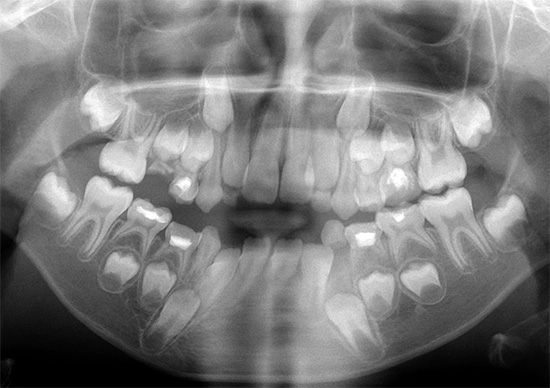

Alla consultazione iniziale, dall'età di 4-5 anni e più, quando i bambini sono già più consapevoli, il medico può riferirti all'immagine: un ortopantomogramma. Ciò contribuirà a valutare le condizioni del sistema dentofacciale, la presenza o l'assenza dei rudimenti di tutti i denti permanenti in un bambino, la posizione delle radici dei denti temporanei e anche lo stadio di sviluppo dei denti. A volte i denti temporanei sono ritardati nella mascella e rappresentano un ostacolo all'uscita di quelli permanenti.

Inoltre, usando l'ortopantomogramma, è possibile valutare la presenza di cavità cariate, la loro profondità, vedere i fuochi del processo infiammatorio nella radice del dente, vedere le condizioni delle strutture ossee sottostanti della mascella superiore e inferiore (seno mascellare, canale mandibolare). Tutto ciò aiuta a pianificare correttamente il corso del trattamento della malocclusione.